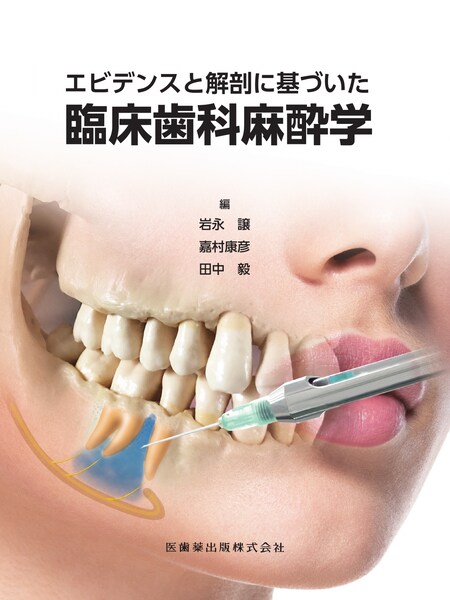

正規激安 | 第4版 無歯顎補綴治療学 市川 力廣 大久保 周治, 大川 哲雄, 歯科学

メーカー | 8b0e21ee15145 | 発売日 | 2025-04-05 02:08 | 定価 | 11410円 | ||